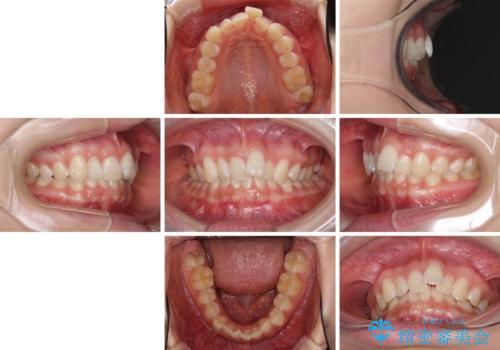

前歯のデコボコを治したい インビザライン矯正治療

- 前歯のデコボコ気になるとのことで来院された患者様です。

下顎骨が上顎骨に対して右側にシフトしており、さらに下顎が後方に位置しているため、非常に強い咬合力で食いしばっている状態でした。

上下顎ともに歯列全体の後方移動とIPR(歯と歯の間を削る)によってデコボコが解消するように設計し、インビザラインにより治療を行うこととしました。

強い咬合力による臼歯部の噛みにくさと、それに伴う歯の移動の鈍さに悩まされ、非常に長い期間を要することとなりました。

上下正中位置は、治療開始時よりは改善したものの、ここが限界であろうというところでのゴールとなりました。

下顎前歯の大半が隠れている状態ですが、左右への歯ぎしりはスムーズに行うことができ、就寝時には後戻り防止も兼ねて、食いしばり対策としてマウスピースの使用を継続するようお願いしております。